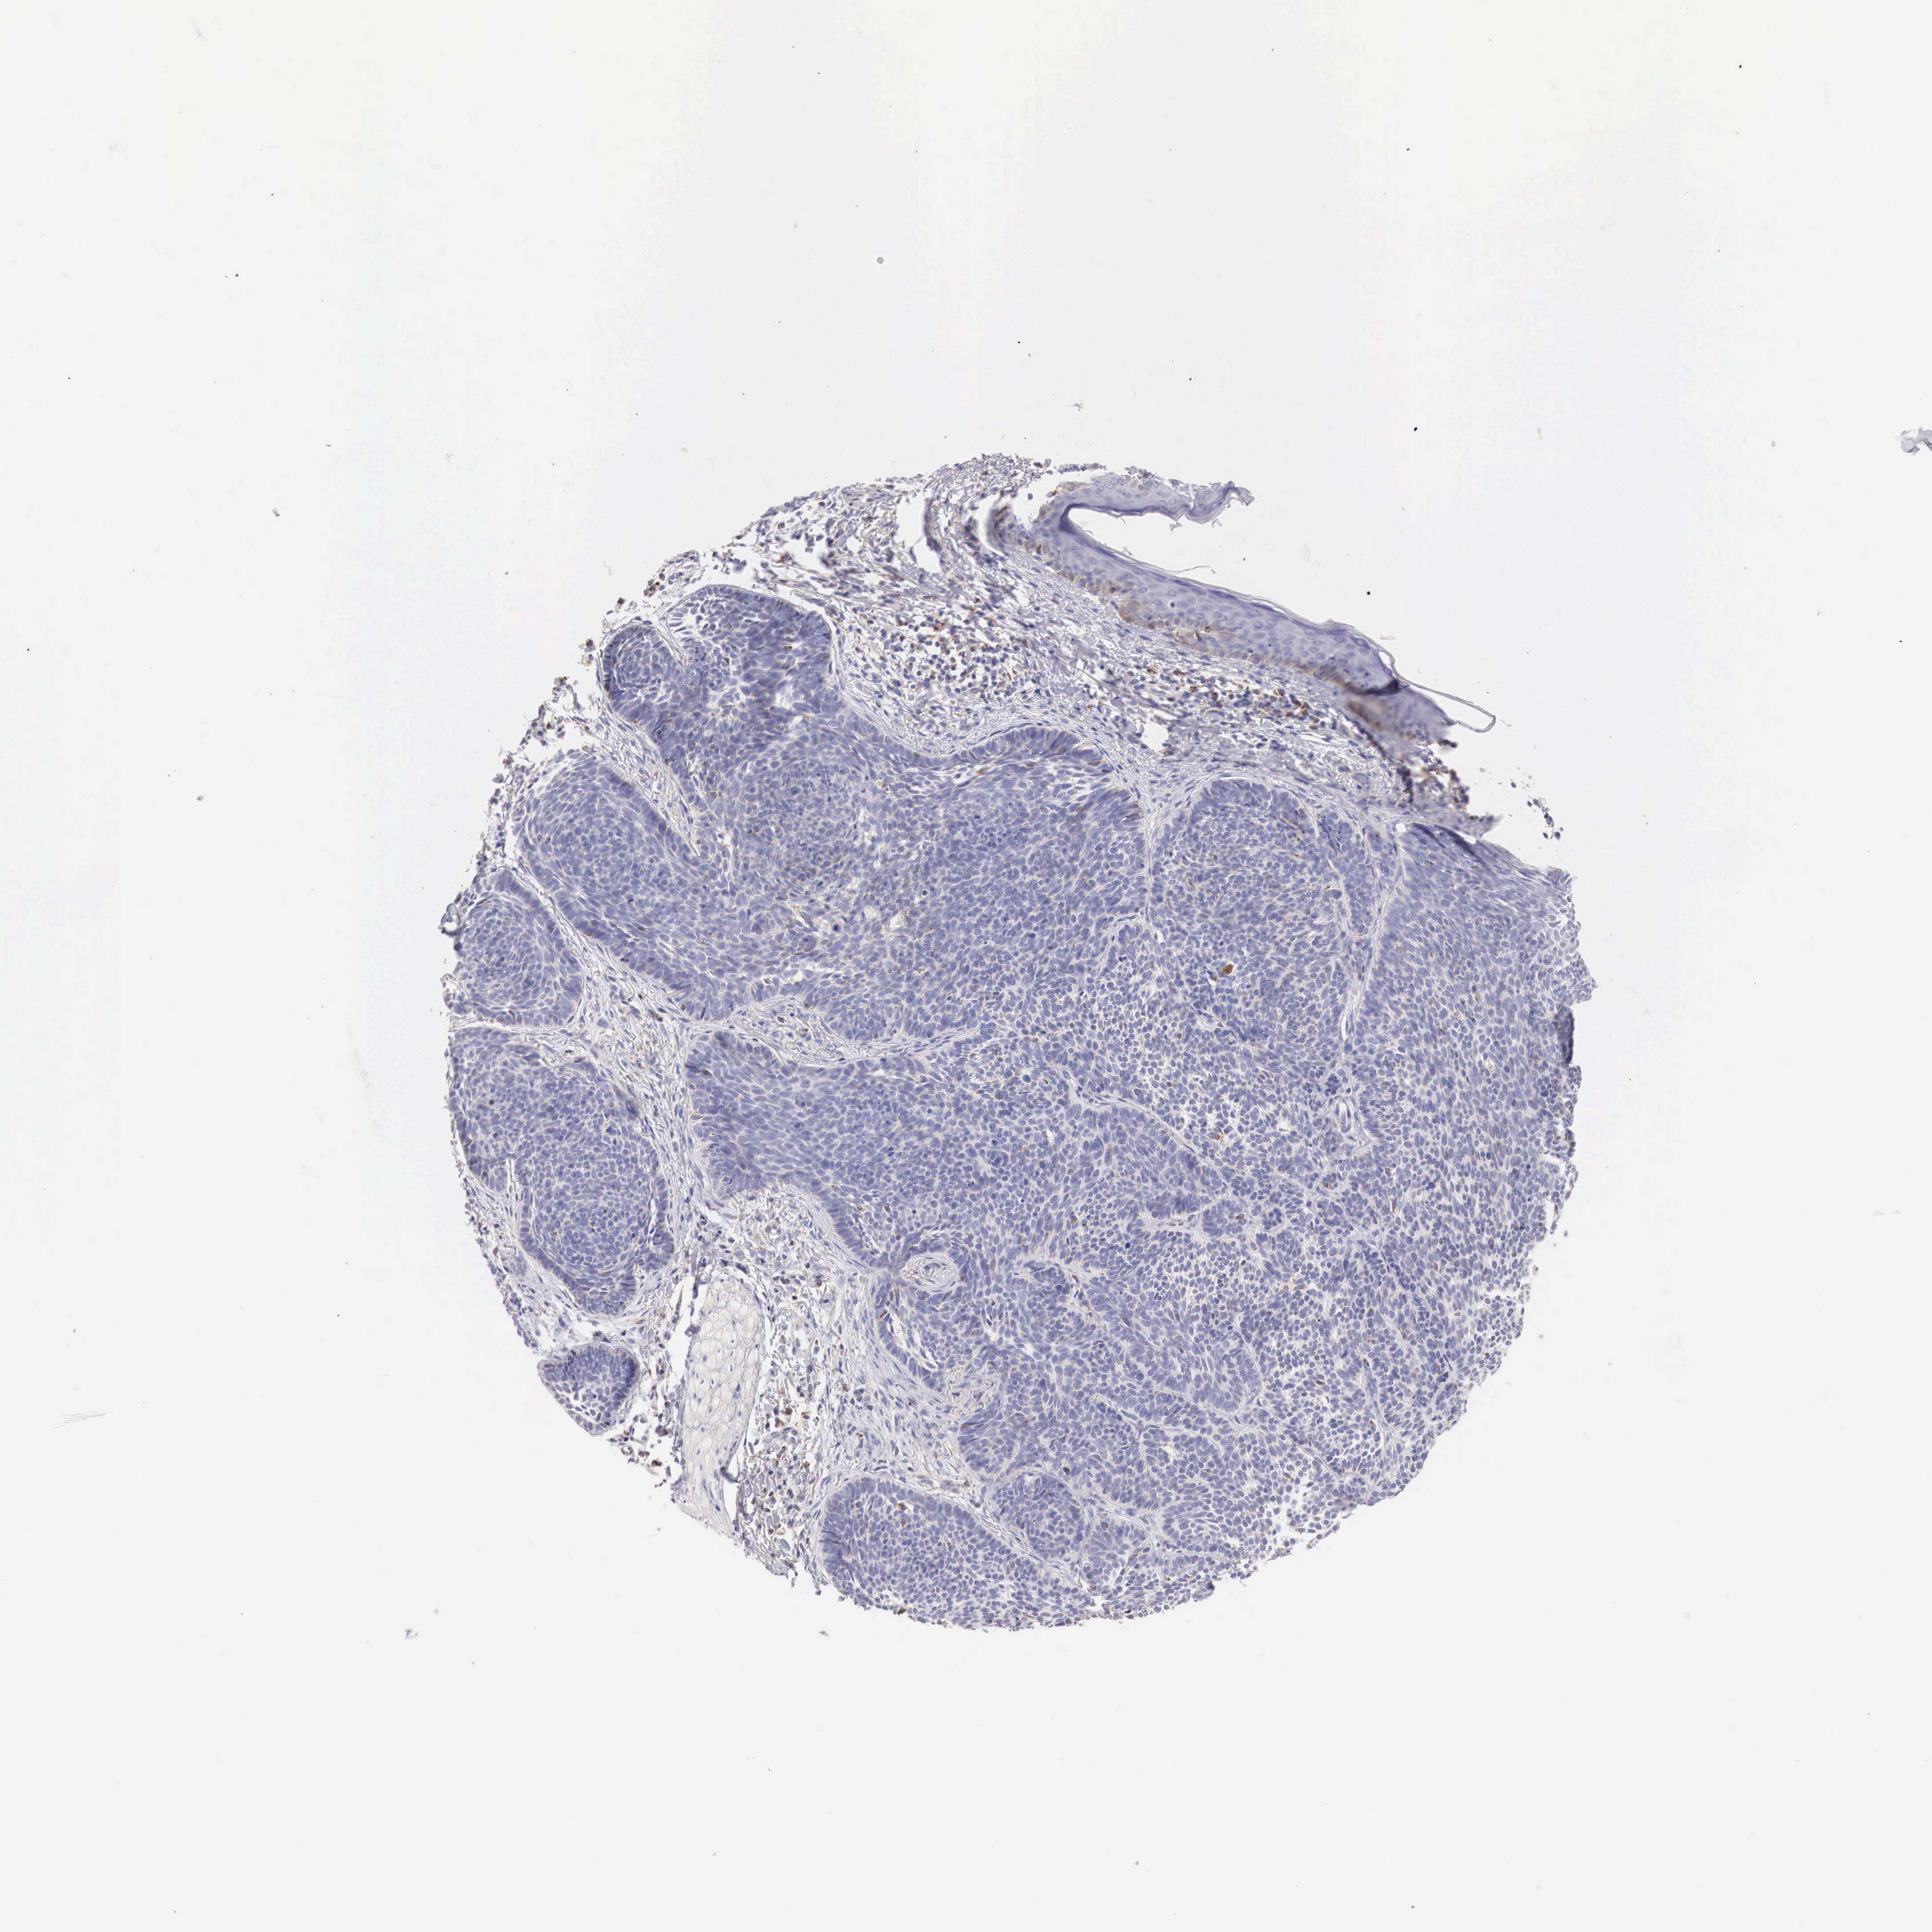

SKIN CANCER - Protein expressioni

A mouse-over function shows sample information and annotation data. Click on an image to view it in a full screen mode. Samples can be filtered based on level of antibody staining by selecting one or several of the following categories: high, medium, low and not detected. The assay and annotation is described here.

Antibody stainingi

Antibody staining in the annotated cell types in the current human tissue is reported as not detected, low, medium, or high, based on conventional immunohistochemistry profiling in selected tissues. This score is based on the combination of the staining intensity and fraction of stained cells.

Each image is clickable and will lead to virtual microscopy that enables deeper exploration of all samples and also displays staining intensity scores, fraction scores and subcellular localization as well as patient and tissue information for each sample.

Antibody HPA000425

Antibody HPA002017

Squamous cell carcinoma, NOS

Basal cell carcinoma